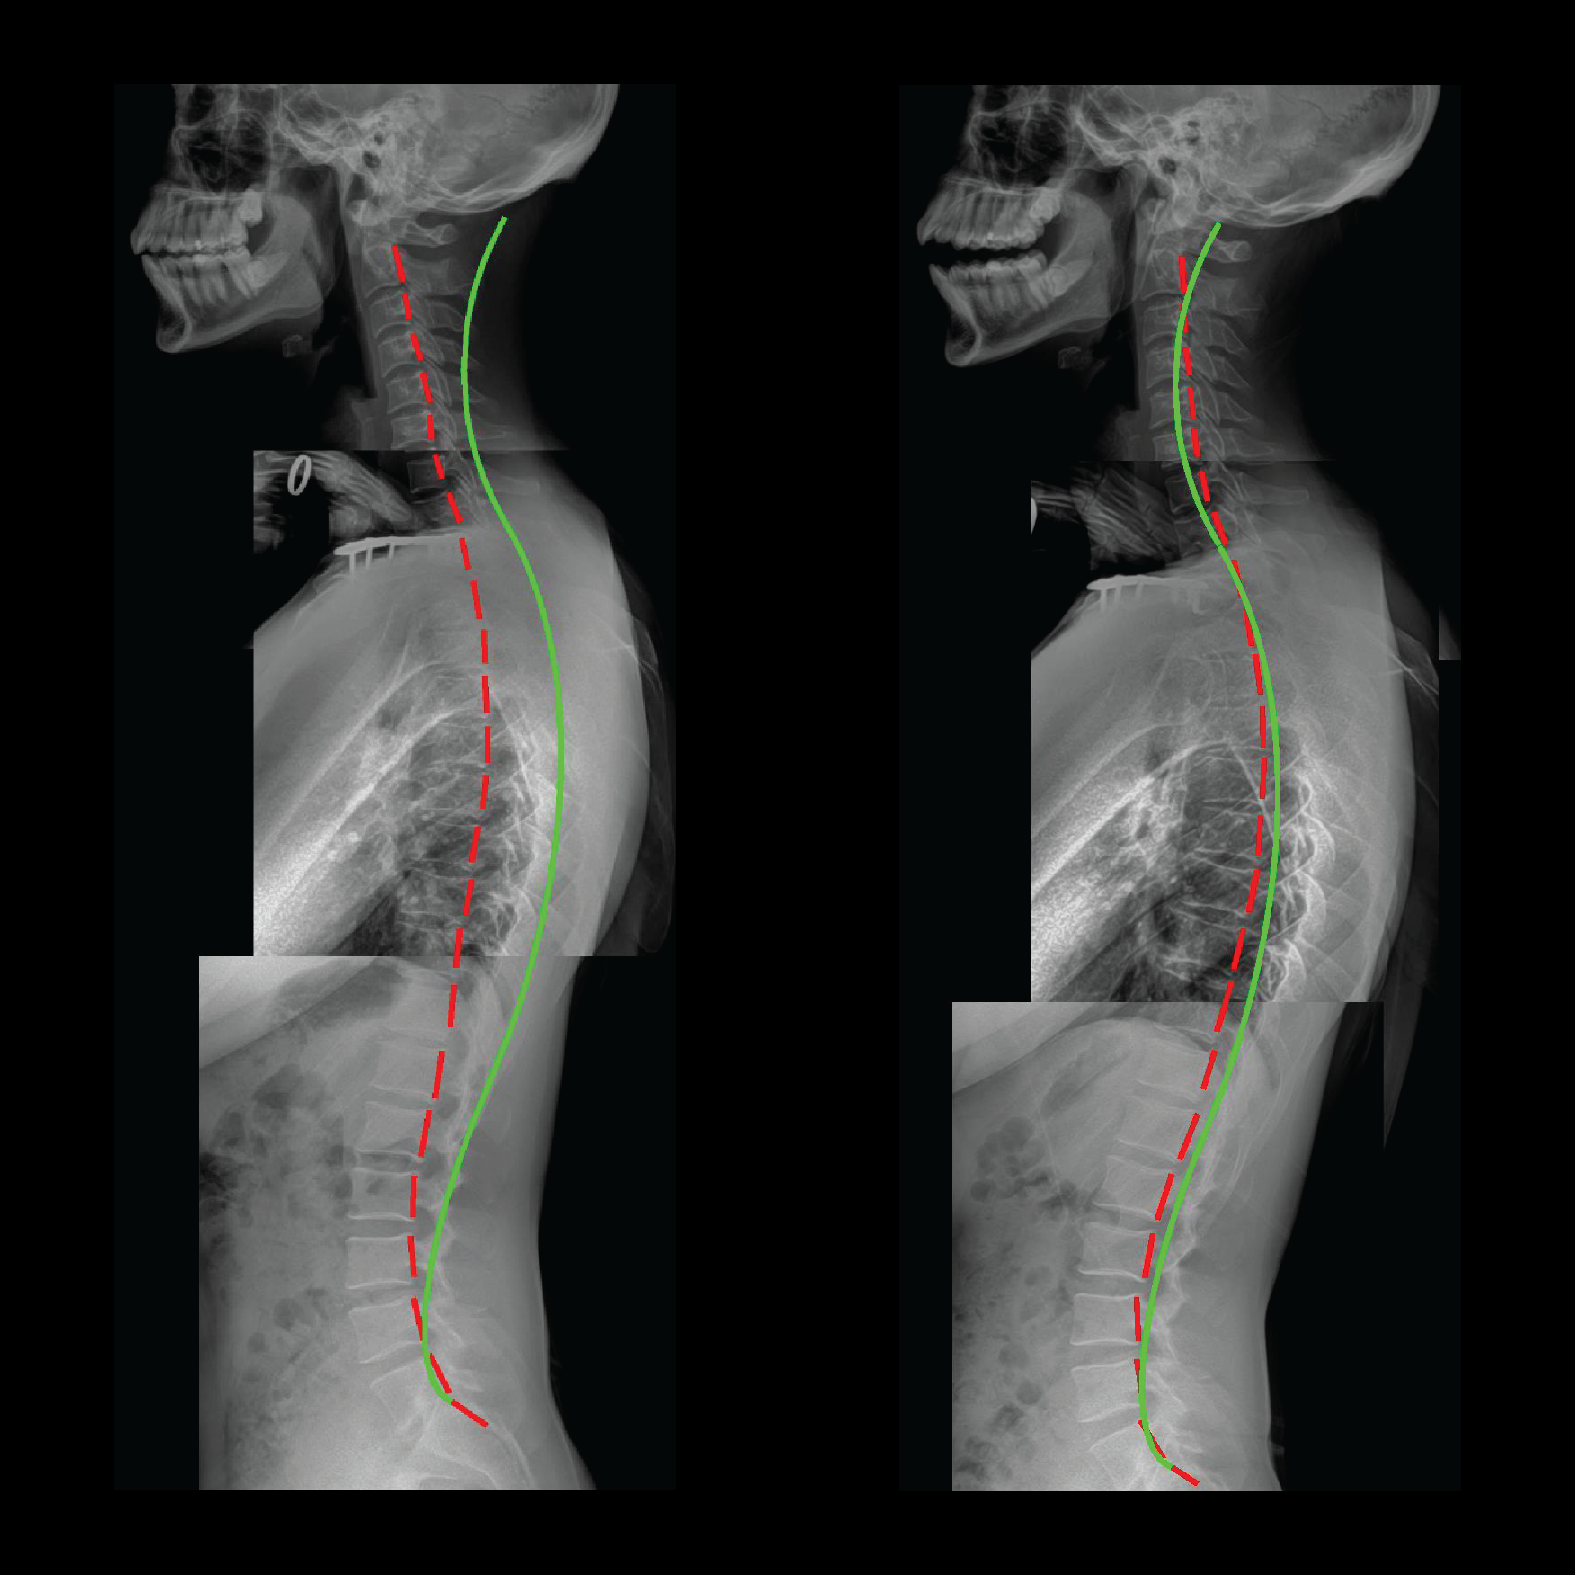

Progress X-Ray

The patient’s spinal curve has improved relieving the patient from her ongoing spinal headaches.